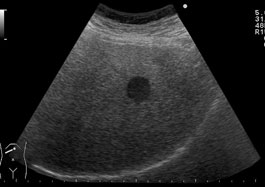

医師は、腎臓の嚢胞を視覚化するために腎臓超音波検査の実行を希望する場合もあります。これは腎臓の損傷の程度を判断するためのものです。